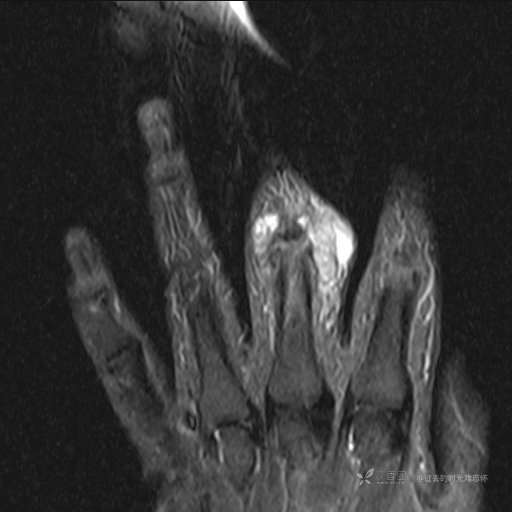

患者性别:女

患者年龄:59岁

主诉: 手指肿胀2年,其间明显肿胀,抗炎后肿胀减轻,近几日肿胀疼痛加重。

T2及T2压脂

提示:小指是伪影。